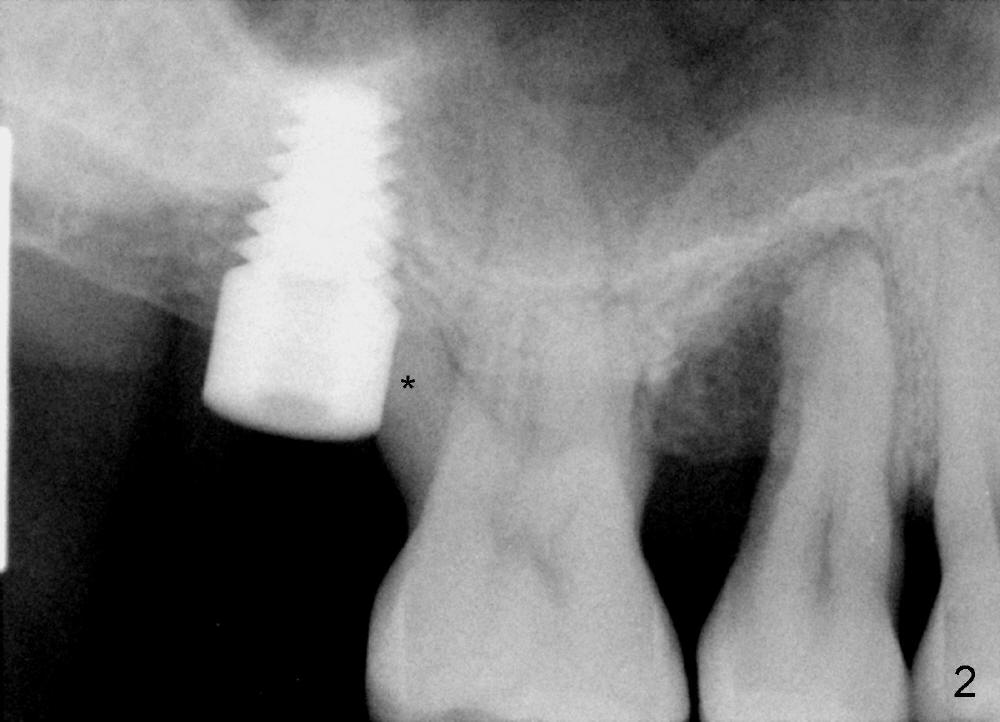

Mr. Kong is 43 years old. He has perio disease, for example #4 (Fig.1). The bone loss may be related to traumatic occlusion. The teeth #2, 14, and 15 are missing. Our primary goal is to restore these missing teeth as soon as possible. The bone height at the site of #2 is 5.8 mm. The Hounsfield units in the oral cortex, medullary and sinus floor are 400, 200 and 500, respectively. A trephine bur with outer diameter of 4 mm was used to start osteotomy (1,2). Probably due to limited access and dense bone, the trephine bur penetrated bone approximately 2 mm. A 2 mm pilot drill was used for further penetration, followed by 2.5-4.0 mm Bicon reamers for cylindrical osteotomy. A 4.5x11 mm tapered tap was used for bone expansion and sinus lift, followed by 5x11 mm tap (Fig.1). At higher magnification, it appears that the sinus floor had been lifted (Fig.1': *). A six by eleven mm tap was used. The apical end of the osteotomy felt to be intact and solid with a slender surgical curette. There was no sign of sinus membrane perforation, as confirmed by nasal blowing test. Harvested bone (from trephine bur and reamers) was pushed as apical as possible. A 6x11 mm implant was placed (Fig.2). It seems that taps/implant-related sinus lift increases the bone height to about 8 mm (Fig.2'). The thread portion of the implant is 6 mm. It appears that the 5x11 mm tap (Fig.1) and the 6x11 mm implant (Fig.2) invade the distobuccal apex of the first molar (*). Clinically there was some distance between them. Preop CT (axial section) may show the point (Fig.3: red circle stands for the implant; *: distobuccal apex of the first molar). The patient returns to office for follow up 1 week postop. The wound is healing normally around the stable implant. There is no percussion tenderness of the tooth #3. No bone resorption is observed 5.5 months postop (Fig.4), 7 months (Fig.5, Jan, 2015), 3.5 years (Fig.6) or 5 years 1 month (Fig.7) post cementation. At #14, bone height is 1-2 mm. Implant placement with sinus graft fails.